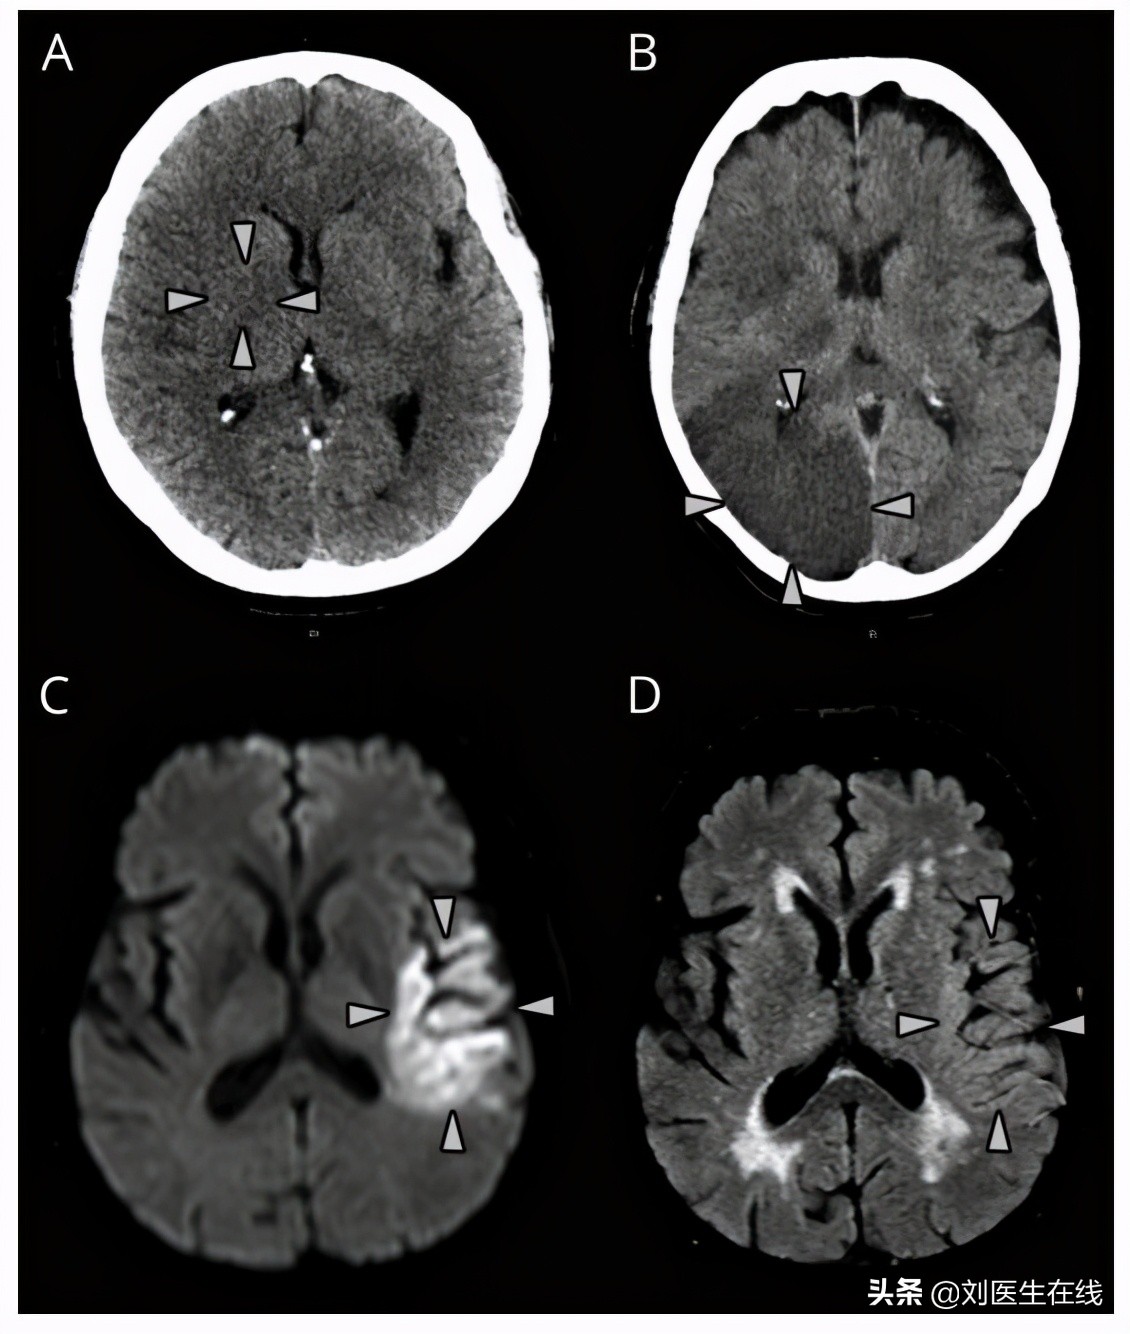

医生在询问王阿姨服药的相关问题,结合CT检查,排除了脑出血。

脑梗依据病因可主要分为大动脉粥样硬化、心源性栓塞和小动脉闭塞三种。

其中,心源性栓塞,也就是堵塞脑部血液循环的这个栓子是来自于心脏部位的。

房颤则是心源性栓塞最常见的原因,房颤时,人体心房的有效收缩功能会明显减弱,给心室的供血量就会变少,同时血液容易在心房内阻滞形成血栓,当栓子脱落之后会随着主动脉进入全身,进而到达颈内和颅内动脉,堵塞脑血管导致脑梗发生。